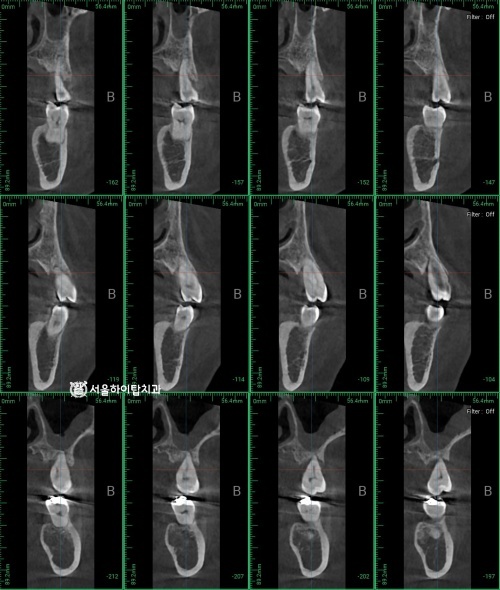

CBCT 촬영 및 계획 수립

먼저 앞서 확인한 3개의 치아 모두 발치가 필요합니다.

이후 임플란트가 진행 되는데, 이때 가장 좋은 방법은

#14, 16에 식립하고 #15 가짜 치아(pontic)로 진행하는 방식입니다.

주안역 치과 에서 그 이유를 알려드리자면,

세 개 치아를 모두 심으면

#15 부위의 골 조건과 교합 부담으로 인해

임플란트 안정성이 떨어질 수 있기 때문입니다.

단, 이 계획을 안전하게 시행하기 위해서는

CT 촬영을 통해 남아 있는 골 양과 질을 반드시 확인해야 됩니다.

왼쪽 사진은 위 부터 순서대로 #14 ~ 16 입니다.

현재 어금니 주변 골의 양과 질이 매우 부족하기 때문에,

임상적으로는 #14와 #15에만 임플란트를 식립하고,

#16은 pontic으로 연결하는 방식이 적합할 것으로 판단됩니다.